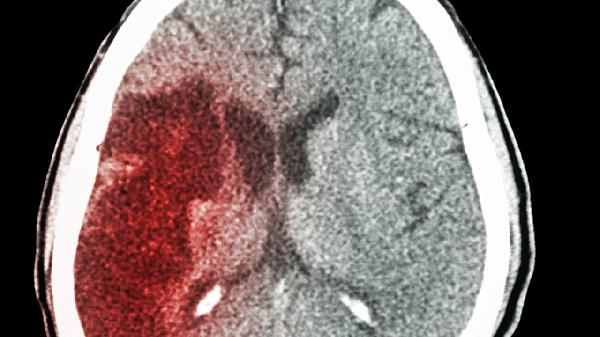

突然出现的头晕、单侧肢体麻木、言语不清等症状,要立即拨打急救电话。